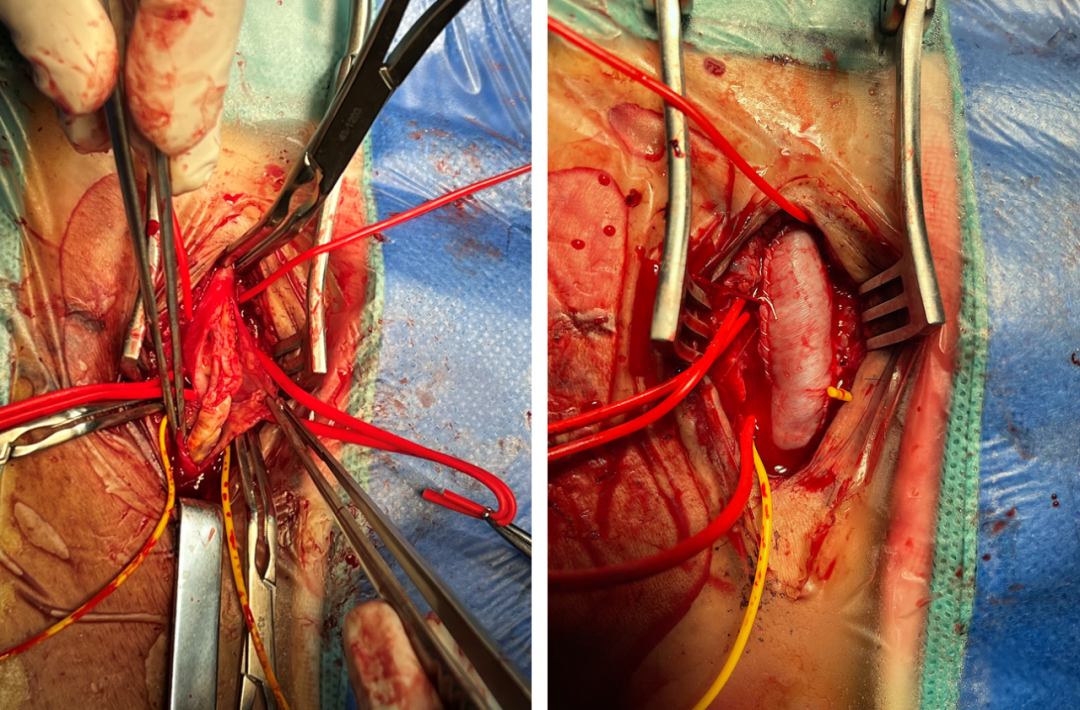

37岁男性,右侧股总动脉瘤

人工血管重建股深和股浅动脉

股总-股浅动脉内膜剥脱+大隐静脉补片

★ Case 5

股总-股浅动脉内膜剥脱+生物补片